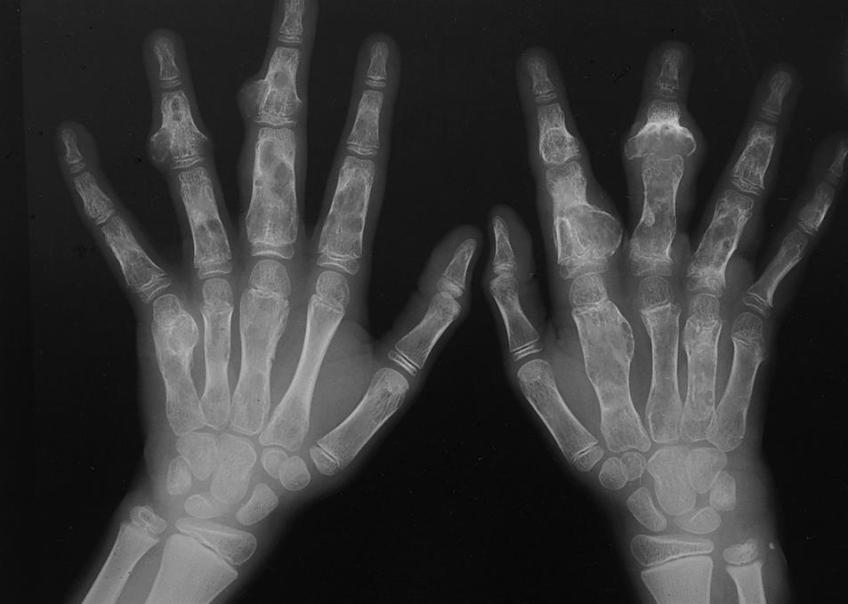

Энхондромы (центральные) – самый распространённый вид хрящевых опухолей. Локализуются в местах, где в норме нет хрящевых тканей, и располагаются внутри кости. Предполагается, что новообразование формируется из остатков хрящевых пластинок, которые со временем постепенно увеличиваются. В процессе развития энхондромы деформируют кость, распирая её изнутри. Обычно образуются в костях кисти (на фалангах пальцев) и стопы. Реже встречаются в подкожной клетчатке и межмышечной ткани, в яичках, в молочной и подчелюстной железе, в околоушной и слёзной железе, в головном мозге, лёгких и яичниках. Чаще всего энхондромы бывают одиночными, но встречаются и множественные – энхондроматоз, который называется ещё болезнью Оллье.

Энхондрому в костях скелета, кроме области основания черепа, можно выявить обычным рентгенологическим исследованием. Например, при локализации подобной опухоли на рёберной дуге слева, сделав рентген, можно увидеть очаг дисплазии и кистозную опухоль. Экхондрома не рентгеноконтрастна, её невозможно разглядеть на рентгеновских снимках на фоне мягких тканей.

Кроме рентгена обычно назначаются следующие исследования: